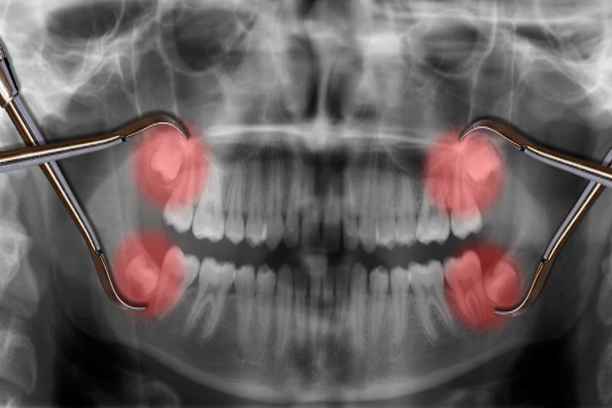

خلع الأسنان هو تدخل طبي يهدف إلى إزالة الضرس المتضرر من جذوره داخل عظم الفك بطريقة آمنة ومضبوطة. التطور في أدوات طب الأسنان جعل العملية أكثر دقة وأقل إزعاجًا مما كانت عليه سابقًا. داخل مركز أضواء الحكمة يتم اتباع خطوات منظمة لضمان أقصى درجات السلامة، وتشمل:

- إجراء فحص سريري شامل لتحديد مدى تضرر الضرس وحالة اللثة والأنسجة المحيطة به، مع الاستعانة بالأشعة عند الحاجة لتوضيح شكل الجذور وعمقها قبل اتخاذ القرار النهائي.

يُستخدم في الحالات التي يكون فيها الضرس مطمورًا أو مكسورًا داخل العظم، ويتطلب فتح اللثة للوصول إليه. يتميز بـ:

- استخدام أدوات جراحية دقيقة للتعامل مع الضرس داخل العظم بشكل آمن ومحكم.

يصبح خلع ضرس العقل جراحيًا ضرورة طبية عندما لا يكون الضرس في وضع يسمح بإزالته بطريقة بسيطة، بل يكون مطمورًا أو مرتبطًا بتعقيدات تشريحية أو التهابية تستدعي تدخلًا جراحيًا دقيقًا. في هذه الحالات، يهدف الإجراء إلى منع المضاعفات المستقبلية وحماية الأسنان المجاورة والأنسجة المحيطة من الضرر المستمر. ومن أبرز الأسباب التي تجعل الخلع الجراحي الخيار الأمثل:

- الانطمار حيث يكون ضرس العقل مدفونًا داخل العظم أو مغطى جزئيًا باللثة، مما يمنع خروجه بشكل طبيعي ويؤدي إلى ضغط مستمر على الأسنان المجاورة وقد يسبب التهابات متكررة، وفي هذه الحالة لا يمكن الوصول إليه إلا بفتح جراحي دقيق لإزالته بأمان.

في مركز أضواء الحكمة لطب وتقويم الأسنان يتم تقييم حالة ضرس العقل بدقة قبل اتخاذ القرار، مع استخدام الأشعة التشخيصية المتقدمة وتحديد أفضل خطة علاجية تناسب كل حالة، لضمان إجراء جراحي آمن ومريح بأعلى معايير الاحترافية.

- إذا تم إجراء تقييم بالأشعة قبل الجراحة لتحديد موقع الجذر والعلاقة مع الأعصاب، تقل احتمالية حدوث مضاعفات.